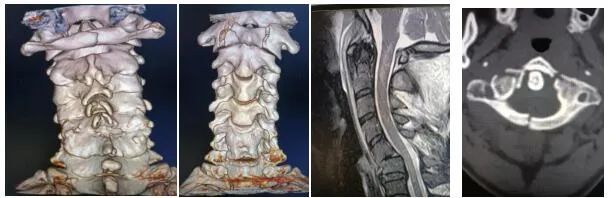

患者男性,50岁,高处坠落致寰椎前后弓骨折并四肢不全瘫,随后到市中心医院就诊,医生在对其进行详细检查后,决定为其实施寰椎骨折切开复位椎弓根钉棒固定术。由于上颈椎解剖结构的特点,手术的风险性较大,特别是需要内固定的手术。加之上颈部疾患常常伴有解剖结构的变异,更增加了上颈椎手术的风险性与难度,开展此类手术必须要经验丰富,技术过硬的医师。

骨一科医生对患者经过全面的术前检查后,严密制定手术方案。由程福宏主任主刀,葛大明副主任医师配合,顺利完成了寰椎骨折切开复位椎弓根钉棒固定术,手术最大可能的减少了固定节段,最大程度的保留了颈椎的活动度,术后患者四肢肌力较术前明显恢复。目前患者已顺利出院,生活可自理。